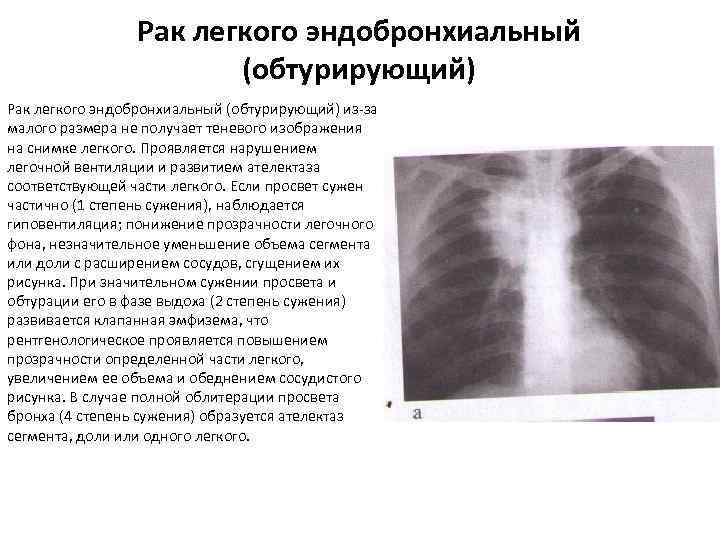

Рак легкого эндобронхиальный (обтурирующий) из-за малого размера не получает теневого изображения на снимке легкого. Проявляется нарушением легочной вентиляции и развитием ателектаза соответствующей части легкого. Если просвет сужен частично (1 степень сужения), наблюдается гиповентиляция; понижение прозрачности легочного фона, незначительное уменьшение объема сегмента или доли с расширением сосудов, сгущением их рисунка. При значительном сужении просвета и обтурации его в фазе выдоха (2 степень сужения) развивается клапанная эмфизема, что рентгенологическое проявляется повышением прозрачности определенной части легкого, увеличением ее объема и обеднением сосудистого рисунка. В случае полной облитерации просвета бронха (4 степень сужения) образуется ателектаз сегмента, доли или одного легкого.

Рак легкого эндобронхиальный (обтурирующий) из-за малого размера не получает теневого изображения на снимке легкого. Проявляется нарушением легочной вентиляции и развитием ателектаза соответствующей части легкого. Если просвет сужен частично (1 степень сужения), наблюдается гиповентиляция; понижение прозрачности легочного фона, незначительное уменьшение объема сегмента или доли с расширением сосудов, сгущением их рисунка. При значительном сужении просвета и обтурации его в фазе выдоха (2 степень сужения) развивается клапанная эмфизема, что рентгенологическое проявляется повышением прозрачности определенной части легкого, увеличением ее объема и обеднением сосудистого рисунка. В случае полной облитерации просвета бронха (4 степень сужения) образуется ателектаз сегмента, доли или одного легкого.